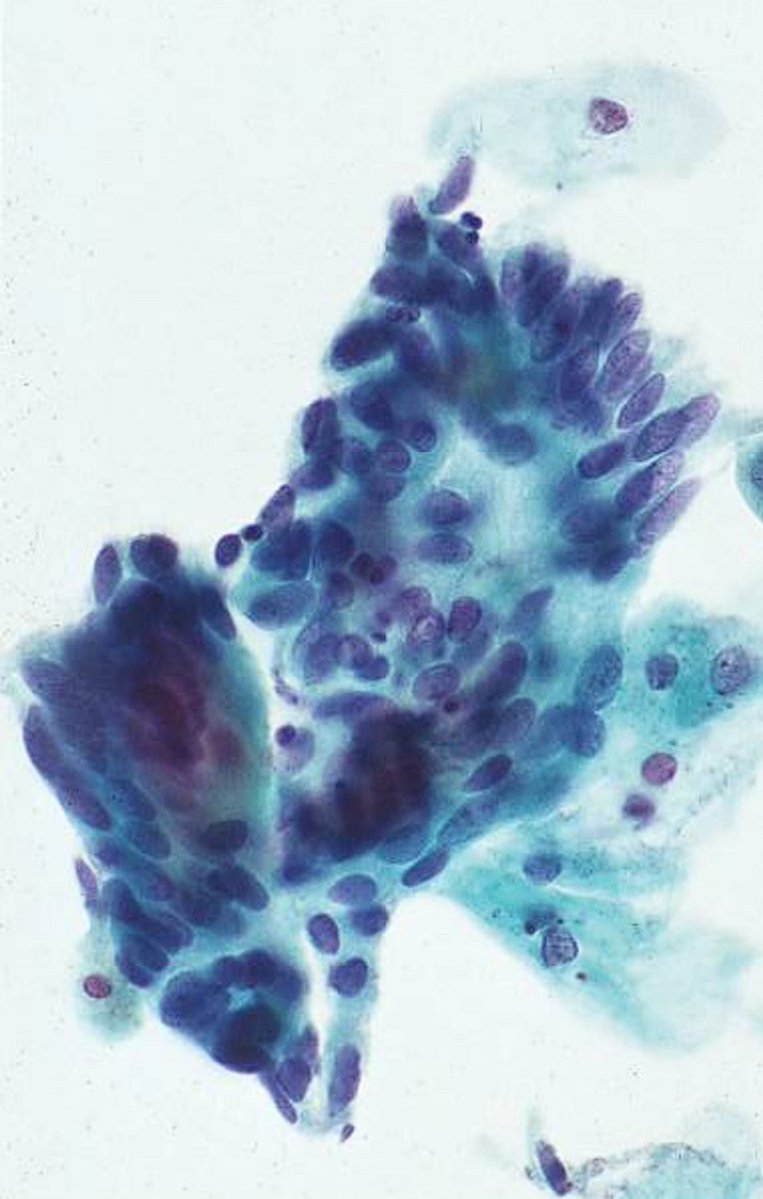

This pap smear from a 35 yo woman with intermenstrual spotting demonstrates atypical __ cells. A) endometrial B) endocervical #CytoPath #PathTwitter #Pathology #GynPath

11

39

121